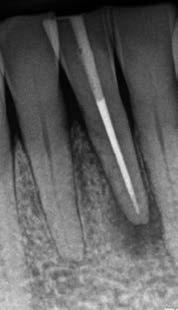

1. a–f ábrák: A cingulumon keresztül gömbfúróval kialakított hozzáférés a trepanációs kavitás labiális irányba történő túlzott mértékű kiterjesztését eredményezheti, és ez lényegesen növelheti a perforáció esélyét (a). A guttapercha átsejlik a lágyrészek alatt (b). Klinikailag igazolt perforáció (c). A preoperatív sagittális irányú CBCT-szeleten jól látható a labiális perforáció (d). Labiális irányú perforáció (fekete nyíl; e). A tényleges gyökércsatorna (piros nyíl; f).

A frontfogakban történő hozzáférési nyílás kialakítása

A frontfogakban a hozzáférési nyílás kialakítását hagyományosan a fogak linguális vagy palatinális felszínén, a cingulumon keresztül egy gömbfúró segítségével kezdjük. A linguálisan elhelyezkedő kiemelkedés teljes eltávolítása, továbbá a pulpaszarvak teljes feltárása egy háromszög alakú hozzáférési nyílást eredményez. 7 Ezt a módszert a fogak esztétikai megjelenésének megőrzése érdekében fejlesztették ki. Ez azonban időnként a saját foganyag indokolatlan eltávolításával, a trepanációs kavitás labiális irányba történő túlzott kiterjesztésével, perforációval, valamint a fog kritikus helyen, a pericervikális dentin (PCD) területén történő meggyengítésével jár (1. a–f és 2. a-b ábrák). 19 Felmerült, hogy a pericervikális dentin rendkívül fontos szerepet játszik a rágóerő gyökerek irányába történő továbbításában, és elképzelhető, hogy a gyökérkezelt fogak hosszú távú megtartása szempontjából a legfontosabb tényező az ép pericervikális dentin megőrzése lehet. 20 A cingulumon keresztül történő hozzáférési nyílás

5. a–l. ábrák: Az incisális élen keresztül kialakított hozzáférés lehetővé teszi a pericervikális dentin megőrzését. Kalcifikáció esetén CBCT-felvétel készítése hasznosnak bizonyulhat a hozzáférési nyílás tervezése során (a–d) . Minden fog koronai helyreállítása a gyökértömés elkészítésével egyidejűleg történt. A négyéves (e–h) és a kétéves (i–l) kontrollok alkalmával készített röntgenfelvételeken teljes gyógyulás látható. Mindkét fog tünetmentes és funkcióképes volt. (Dr. Viraj Vora esetei)

Szuvas lézión keresztül történő hozzáférés (a). A fog koronai helyreállítása a gyökértömés elkészítésével egyidejűleg történt (b és c). (Dr. Dale Jung esete)

kialakítása során fennáll a fog labiális irányú perforációjának veszélye, mivel ilyenkor a foganyag elvételét labiális irányú fúrótartással kezdjük. Nemrégiben újragondolták a

hozzáférési nyílás kialakítási protokollt, amelyet már ko

rábban, két endodonciai közleményben közzétettek. Ezekben a frontfogak hozzáférési nyílásainak kialakítását inci

sálisabb megközelítéssel javasolták. 21,22 Az új ajánlásban azt javasolják, hogy a frontfogakban történő hozzáférési nyílás kialakítását a cingulumtól távolabb, inkább az incizális él közelében kezdjük meg 19. Ez lehetővé teszi a lehető legtöbb pericervikális dentin megőrzését és kizárólag a legszükségesebb mennyiségű dentin kerül eltávolításra. Emellett ez a kialakítás a cingulumon keresztül történő hozzáféréshez képest egyenesebb hozzáférést biztosít a labiális és a linguális, vagy palatinális csatornákhoz, valamint lehetővé teszi a csatornák hatékonyabb tisztítását. 21 A fogak kopása esetén a hozzáférést az incisális „felszín” közepén alakítjuk ki (3. a-b ábrák) . A frontfogak kezelése során a megfelelő fúró kiválasztása is kiemelkedően fontos szereppel bír. A korábban ajánlott gömbfúrók használata ma már kifejezetten kontraindikáltnak számít. A gömbfúrók használatakor jellemzően egy fordított tölcsér alakú üreg kerül kialakításra. Ezekben az esetekben az üreg egyre szélesebb lesz, ahogy egyre mélyebbre hatolunk a fúrónkkal (2. a-b ábrák) 23 A gömbfúrók helyett olyan fúrók használata javasolt, amellyel elkerülhető lehet a trepanációs kavitás túlzott mértékű kiterjesztése, és amely segítségével a hozzáférési nyílás legszűkebb részét a pericer -

zésére. Ez azért fontos, mert a frontfogak funkcionális megterhelése során – a PCD-nek megfelelően elhelyezkedő területben – jelentős stressz ébred (5. a–l ábrák) 24 Szükség esetén egy CBCT-felvételt is készíthetünk. A 3D-s adatok jelentős mértékben segíthetik a klinikus munkáját a gyökércsatorna koronális vetületének vizualizálásában, és ennek alapján az egyenes vonalú hozzáférés biztosításához szükséges belépési pont meghatározásában (5.

a–l ábrák) . Ha a kofferdám izolálás a szomszédos fogakra is kiterjesztésre kerül, úgy a kezelést végző orvos sokkal magabiztosabban tudja a gyökerek angulációját vizualizálni (3. a-b ábrák)